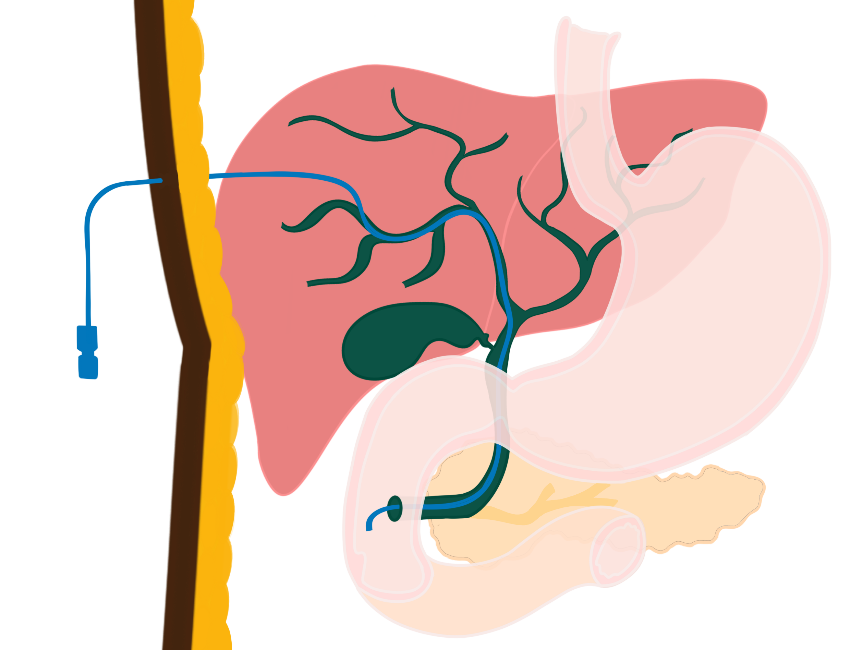

Indien dit weer niet lukt kan een EUS-geleide drainage worden verricht. Of er wordt een slangetje via de buikwand geplaatst, dit noemen we een PTCD (figuur 3).

Figuur 3. PTCD

Het nadeel van een PTCD is dat er tenminste tijdelijk gal via een drain (slang) vanuit de buikwand naar een zakje buiten het lichaam afloopt. Daarom wordt PTCD tegenwoordig zelden als eerste keus ingezet.